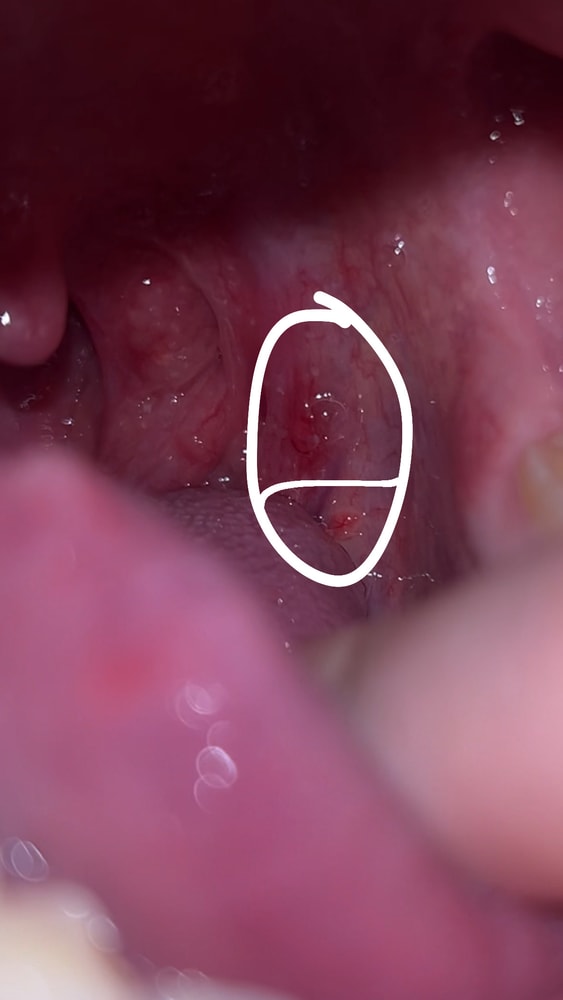

Бородавки? Фарингит?

сегодня было несколько болезненно глотать и заметила эти образования. Они на фото выглядят более сглажено в Реале торчат над кожей

В горле мы не ждем бородавок, а только кондилом после контакта с инфицированным пенисом. На фото наверное просто гиперплазия от воспаления.